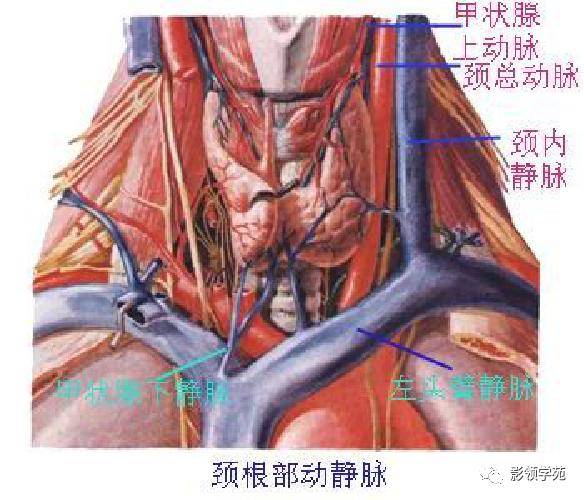

心血管系统

心血管系统